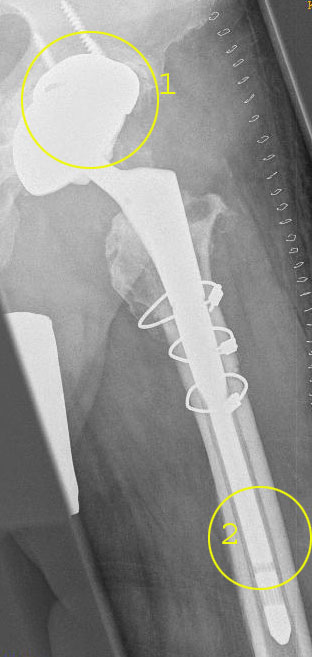

Periprothetische Femurfraktur: Oberschenkelbruch oder Beckenbruch nahe dem Implantat

Periprothetische Frakturen – Knochenbrüche an der Prothese – betreffen meist ältere Patienten und sind Folge von Stürzen. Je älter der Patient, umso wahrscheinlicher wird eine Fraktur der Prothese. Neurologische Begleiterkrankungen können das Risiko zusätzlich steigern. Allerdings können auch gelockerte Prothesenteile ohne Sturz zu Knochenfrakturen (v. a. Stressfrakturen) unter Belastung im Alltag führen. Osteoporose (Knochenschwund) erhöht das Risiko der Prothesenfraktur ebenfalls deutlich.

Die Wahrscheinlichkeit von Prothesenfrakturen ist umso höher, je länger die Erstimplantation zurückliegt. Am häufigsten bricht der Knochen bei einliegender Hüftprothese im Bereich des Femurs (Oberschenkelknochen). Ein solcher Knochenbruch führt zur Instabilität. Die Verankerung der Prothese kann sich lockern, sodass diese ausgetauscht werden muss.

Um einen periprothetischen Bruch zu diagnostizieren, bringt die Anamnese (Erhebung der Krankengeschichte) klare Hinweise auf den Unfallhergang. Der Patient schildert zudem die typischen Symptome einer periprothetischen Fraktur (PPF): Belastungsschmerzen, Ruheschmerzen und Funktionseinschränkungen. Bei der Inspektion kann die Beinachse bereits verändert sein. Im Röntgen erkennt der Arzt oft schon die Frakturlinien und Lysesäume, also die Bereiche, wo in Prothesennähe die Knochendichte bereits vermindert ist. In Einzelfällen ist eine weitergehende Untersuchung der Fraktur mittels Computertomografie (CT) erforderlich.

Bei der operativen Behandlung der periprothetischen Fraktur soll aufgrund des meist fortgeschrittenen Alters des Patienten auf jeden Fall eine frühe Mobilisation möglich sein. Wir verfolgen daher das Ziel, durch eine geeignete Technik eine Vollbelastung ab dem Operationstag zu ermöglichen (frühfunktionelle Mobilisation).

Daher versorgen wir periprothetische Knochenbrüche mit winkelstabilen Platten (operative Osteosynthese). Diese weichteilschonenden Platten verbinden die Bruchstellen und stabilisieren sie. Wenn die Prothese bzw. der Prothesenschaft selbst nicht gelockert ist, genügt die Stabilisierung der Bruchstelle durch Platten.

Bei einer Lockerung des Prothesenschaftes wird zusätzlich die Prothese ausgetauscht. Ein solcher Prothesenwechsel muss schnell für Belastbarkeit sorgen und gleichzeitig die Hüftprothese langfristig stabil befestigen.